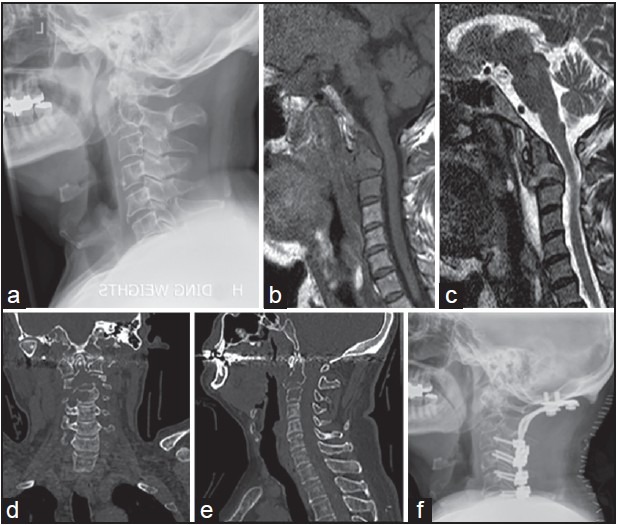

Figure 2.

images from Patient 2. Pre-operative lateral radiograph (a). MRI (b and c) and CT (d and e) are part of the standard work-up prior to surgical stabilization with post-operative images (f)